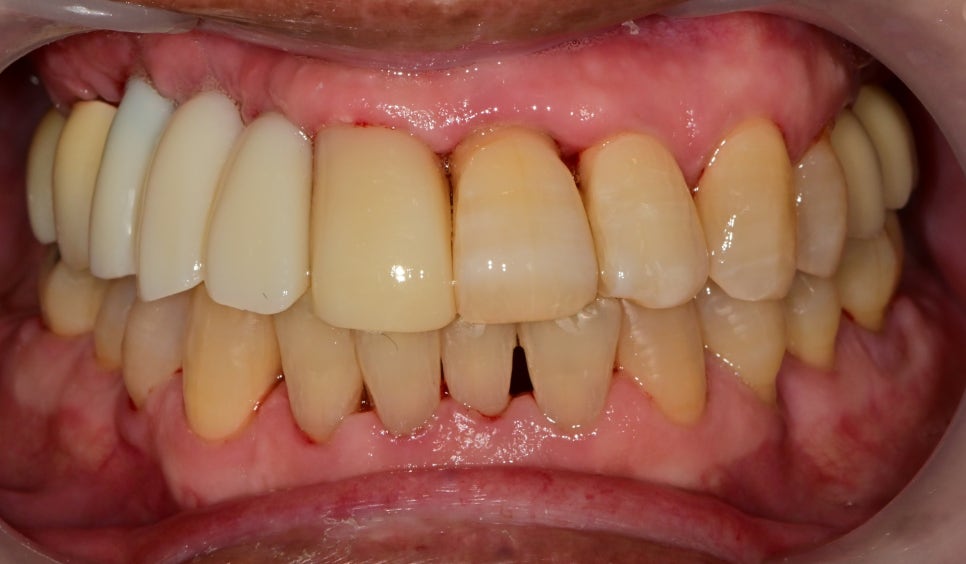

어금니의 임플란트의 고정이 향상되고 치아가 하나둘씩 들어가며

흔들리던 앞니도 발치 없이 사용할 수 있게 되었습니다.

처음 수술했던 임플란트들은 뼈와 고정력이 높아져 임시치아부터 사용했습니다.

그와 동시에 염증이 너무 깊어 수술하지 못한 곳을 오랜만에 오신 김에 수술하기로 했습니다

최종 보철물이 아니고 급하게 제작된 임시치아기 때문에

모양이나 색상이 투박하지만 최종 보철까지 시간 동안

어색함 없이 사용이 가능할 것입니다.

임시치아를 사용하는 이유는

빈 공간을 가리기 위함도 있지만

최종 보철물을 제작할 때 치아의 형태, 색상, 길이 등 수정사항을 통해

추후 보철물 제작에 반영하기 위해 사용하는 것도 이유입니다.

현재는 환자분께서 어금니가 없는 상태를 오랫동안 유지했기 때문에

턱관절의 적응 기간이라 가끔 서울을 방문하셔서 체크를 하고 있습니다.